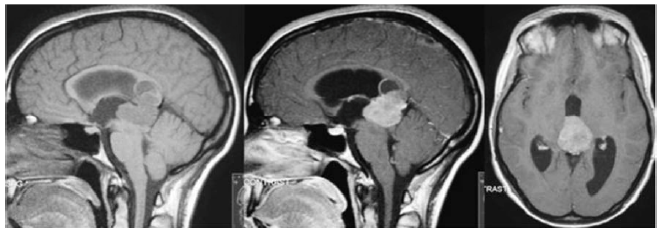

Uma paciente de 62 anos de idade, com queixa de cefaleia há seis meses, evoluindo, há uma semana, com hemiparesia à esquerda (confirmada ao exame físico, com força grau III em membro inferior e grau IV em membro superior), realizou ressonância magnética de crânio com contraste, que evidenciou lesão intradural, extra-axial, localizada na convexidade frontal direita, medindo 5 cm de diâmetro, com intenso realce pelo meio de contraste e compressão do parênquima cerebral adjacente. Foi então submetida à ressecção da lesão, sendo o material encaminhado para análise histopatológica e imuno-histoquímica.